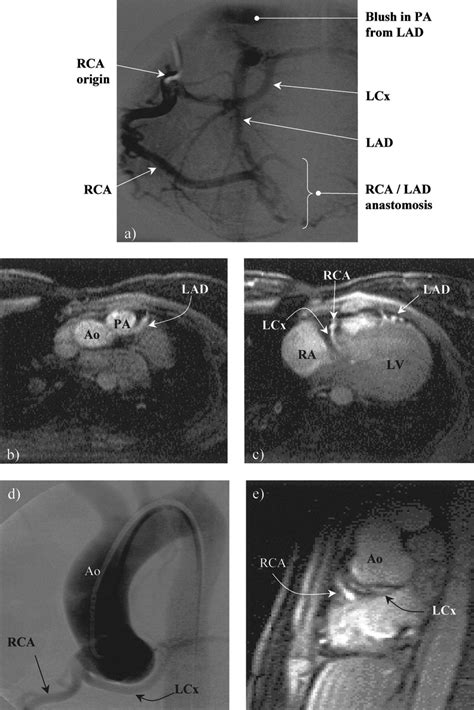

We hope you will use this picture in the study and. The major epicardial vessels are the left main. You can click the image to magnify if you cannot see clearly. Anatomy of coronary sinus and clinical application— presentation transcript 9 developmental anatomy of the coronary sinus (cs) (26 weeks)—the right horn of the sinus venosus remains as the venous portion of the right atrium between the vena cava. The coronary sinus is a collection of smaller veins that merge together to form the sinus (or large vessel), which is located along the heart's posterior (rear) surface between the left ventricle and left atrium. The endpoint of coronary flow and is continuous with the right atrium. Anatomy of coronary circulation email protected edu.my. 3 anomalous origin of a coronary (aoca) from the opposite sinus of valsalva. The cavernous sinus is a paired dural venous sinus located within the cranial cavity. The image on the right shows. Coronarography of the right and left coronary arteries and ventriculography, with 3d modelling of the heart and of the different radiological planes. Coronary sulcus and empties into the right atrium. Great cardiac vein middle cardiac vein small cardiac vein.